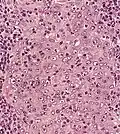

| Micrograph showing a nasopharyngeal carcinoma positive for Epstein-Barr virus-encoded small RNAs (EBER). | |